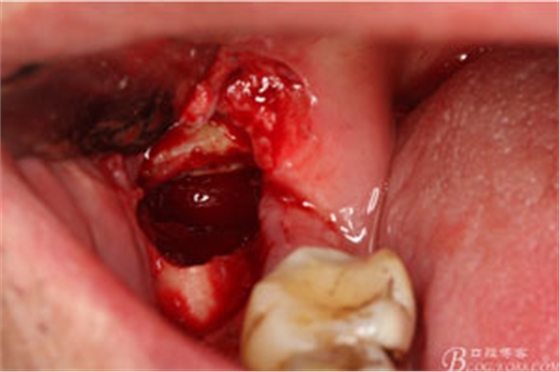

圖6.行角形瓣切開、翻瓣、暴露骨面,可見48牙冠表面有炎性肉芽組織